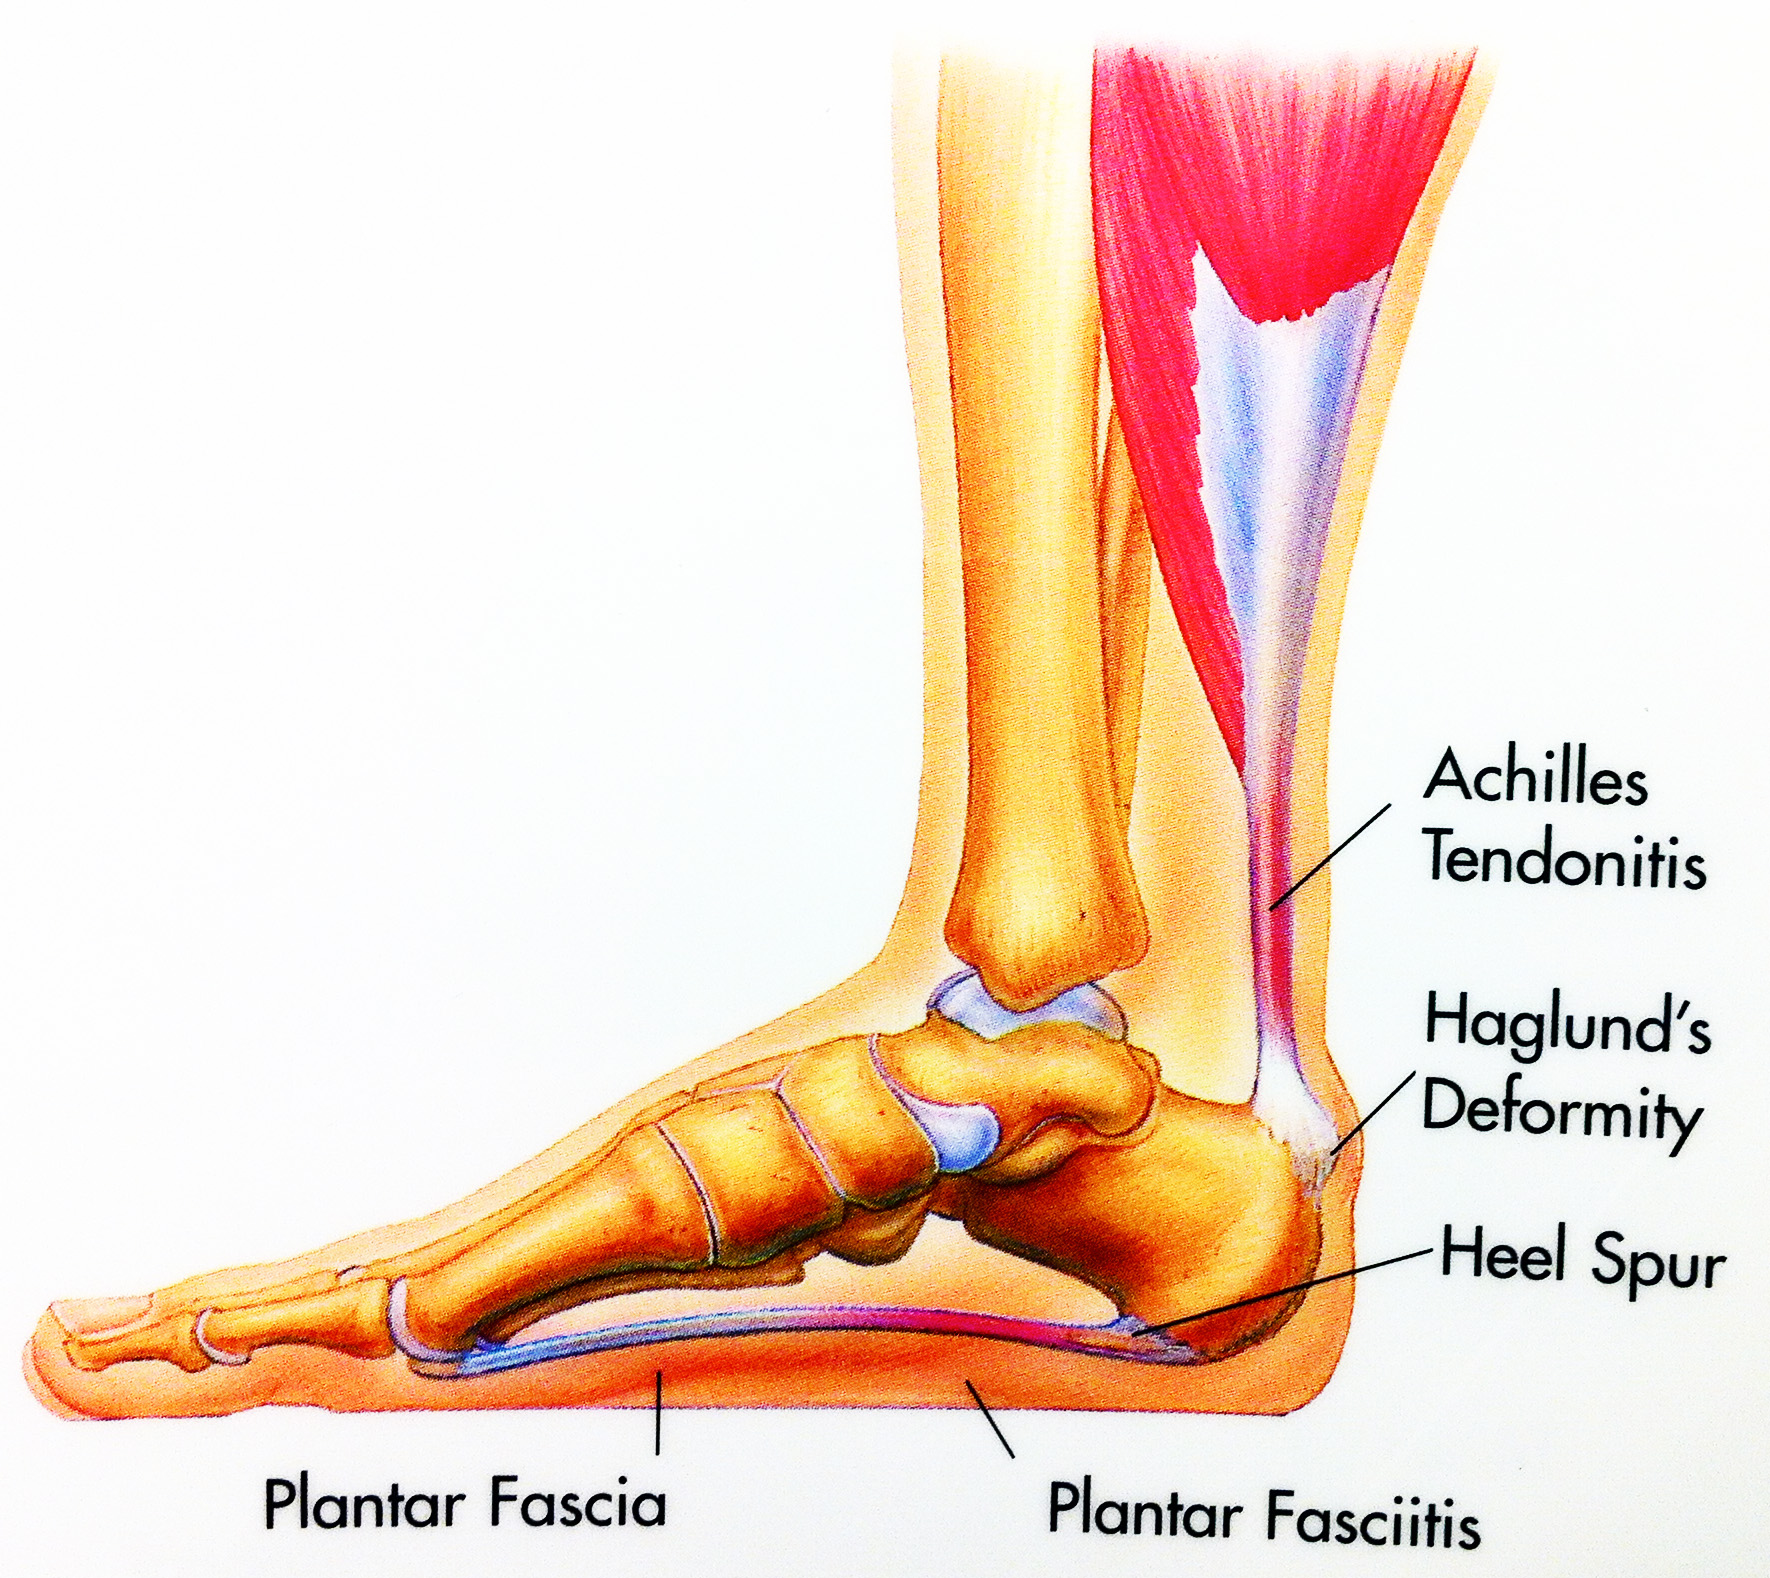

Achilles Heel, Achilles Tendon, Achilles Tendonitis Explained. Achilles …

💥𝐀𝐜𝐡𝐢𝐥𝐥𝐞𝐬 𝐓𝐞𝐧𝐝𝐢𝐧𝐨𝐩𝐚𝐭𝐡𝐲💥 ——— 👣Achilles tendinopathy describes a …

What is Achilles Tendinopathy? – Insoles and Orthotics – Healthy Step

Achilles Tendinopathy (Tendinitis and Tendinosis) – Complete Feet …

Achilles Tendinitis – Procare Podiatric Medicine & Surgery

Achilles Tendinopathy | Mr Daniel Goldbloom | Melbourne

Retrocalcaneal Bursitis: Causes, Symptoms & Treatment